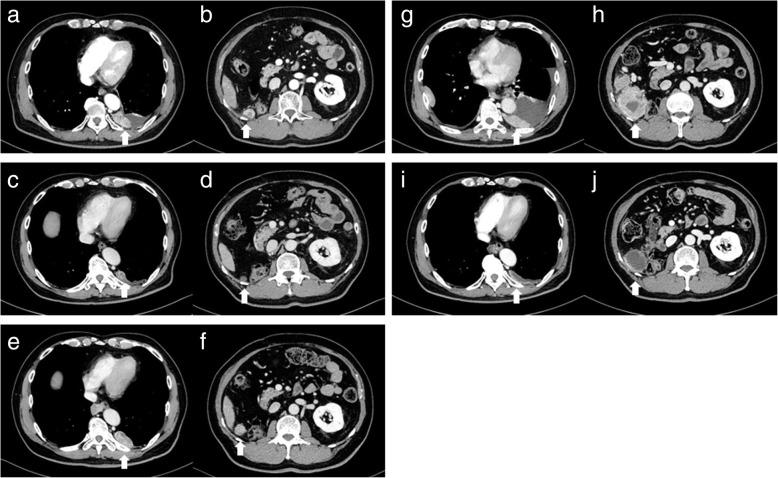

A 66-year-old Japanese man with metastatic renal cell carcinoma became refractory to interferon α and sunitinib therapies. He started treatment with axitinib at 10 mg/day, and the dose was gradually tapered down to 4 mg/day because of intolerable adverse events. His metastatic lesions shrank; however, he could not continue due to the adverse events. He started fourth-line therapy with nivolumab; however, the metastatic lesions increased. Rechallenge with axitinib 4 mg/day was started, and the dose was reduced to 2 mg/day because of adverse events. Subsequently, the adverse events became controllable, and the metastatic lesions were maintained at reduced size.

一名66岁的日本转移性肾细胞癌男性患者对干扰素α和舒尼替尼治疗产生耐药。他开始接受阿昔替尼治疗,剂量为每日10毫克,由于无法耐受的不良事件,剂量逐渐减至每日4毫克。他的转移病灶缩小;然而,由于不良事件,他无法继续治疗。他开始接受纳武单抗的四线治疗;然而,转移病灶增加。再次开始使用每日4毫克的阿昔替尼治疗,由于不良事件,剂量减至每日2毫克。随后,不良事件得到控制,转移病灶维持在缩小后的大小。